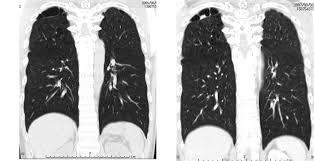

A pet scan is not specific for cancer. It also can let you and your doctors know if cancer treatment is working. The scanner detects diseased cells that absorb. With that being said, not all cancers can be detected by pet. A pet scan, which uses a small amount of radioactive material, can help show if an enlarged lymph node is cancerous and detect cancer cells throughout the body that may not be seen on a ct scan. Positron emission tomography (pet) imaging scans use a radioactive tracer to check for signs of cancer, heart disease and brain disorders. The pet scan detects the concentrated psma tracer, pinpointing these tumors for more effective treatment. Psma pet imaging is a fda approved scan with more precise detection of prostate cancer for better treatment planning and targeted care. Most pet scans use a type of radiolabeled sugar to detect the cancer, as the majority of cancers grow quickly and need sugar for that growth. Pet can detect extremely small cancerous tumors, subtle changes of the brain and heart, and give doctors important early although cancer spreads silently in the body, pet can inspect all organs of the body for cancer in a single examination. Pet scans, short for positron emission tomography, can detect areas of cancer by obtaining images of the body's cells as they work. Ultrasound is also used to image the abdominal organs and kidneys. To determine whether the cancer has spread.

Those are detected by pet scanner and a computer converts a signal into detailed images showing how organs are working. Pet is speeding the detection of new drug weapons in the war on cancer. The tracer will collect in areas of. Positron emission tomography (pet) imaging or pet scan is a nuclear medicine imaging. Pet scans use radioactively tagged molecules (or tracers) to image a wide array of molecular processes and when detected by a pet scanner, the tracers help your doctor to see how well your organs and tissues are working. Pet scans are a type of test that create 3 dimensional (3d) pictures of the inside of your body. Pet scan is a special type of imaging test in which tracers are injected & are absorbed into organs of body and images are obtained. For cancer and disease detection, the most commonly used nuclear scan is an fdg pet scan. The pet scanner detects signals that are given off from the tracer. Pet/ct, which is a combination of positron emission tomography (pet) with computerized tomography (ct), is a powerful, essential tool for cancer detection and diagnosis. Diagnosis, cancer staging, treatment diagnosed with cancer and are undergoing active treatment, assess treatment response efficiency and perform cancer monitoring with pet/ct scan! A pet scan is not specific for cancer. With that being said, not all cancers can be detected by pet.

Scheduled to get a pet scan? Because of this high level of chemical activity, cancer cells the combined use of pet scans and ct scans is an effective method for detecting pelvic recurrences of rectal cancer. Prostate cancer that spreads or comes back after treatment is often small and hard to detect. For cancer and disease detection, the most commonly used nuclear scan is an fdg pet scan. Nuclear medicine images use a small quantity of a radioactive substance to detect, evaluate, or treat various diseases.